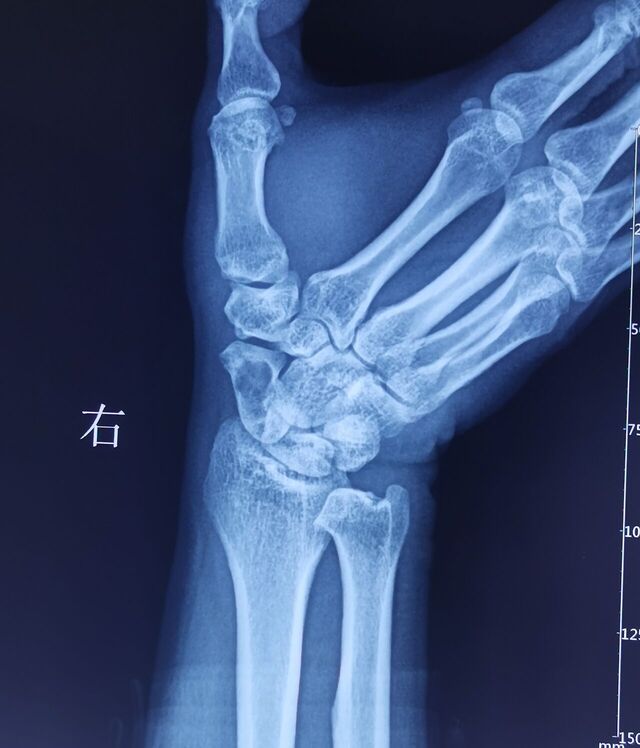

腕关节骨性关节炎

SLAC分期:

I期,舟骨窝局限性关节炎始于桡骨茎突

II期,发展到近端舟骨窝

III期,进而出现头月关节炎

IV期,全腕关节炎

该病例需要做CT重建

判断腕关节骨性关节炎分期

根据分期决定具体术式